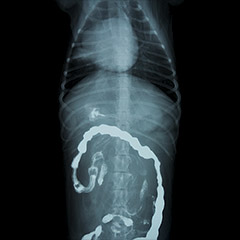

造影検査は、レントゲン検査が苦手としている腹部の臓器を中心に、造影剤というものを用いて、臓器を浮き彫りにすることで、通常のレントゲン検査では判別しづらい異常を把握するのに役立ちます。中でも、動物病院では経口的にバリウムを投与し、消化管(食道~直腸まで)の状態を確認する検査が一番よく行われます(消化管バリウム造影)。これは、動物では誤食が多いためで、異物による閉塞の確認に用いるからです。通常のレントゲンは撮影~現像に少しお時間がかかるので、撮影枚数にもよりますが、通常15~30分程度で診断可能です。

一方、消化管バリウム造影検査は、時間を追って食道から直腸までのバリウムの流れを数分おき、または数時間おきに、コマ送りのように撮影して、確認していきますので、1日~2日かけて行います。そのため、動物のお預かりが必要となります。